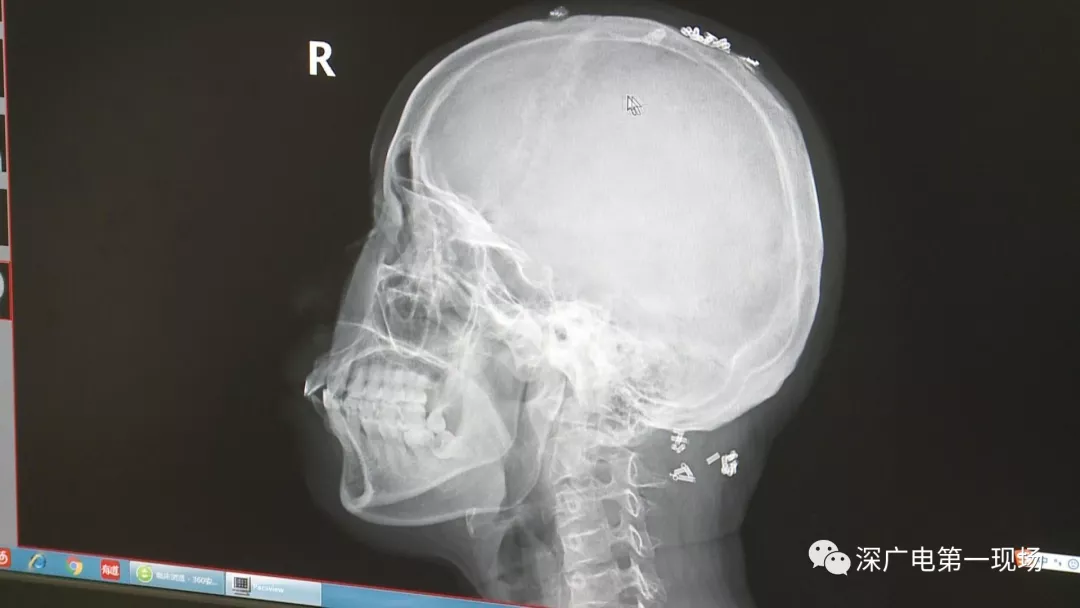

從X光影像圖片中可以看到

患者周身布滿了彈簧圈

深圳大學總醫(yī)院神經(jīng)外科副主任醫(yī)師陳富勇介紹,當時檢查的時候發(fā)現(xiàn),該患者從頭部到腿部,基本上每個地方都有彈簧,很難數(shù)清具體數(shù)目。

陶主任表示,將這些彈簧圈取出也是一項大的工程,因為有的都已經(jīng)形成了包塊,所以想要取出還得先定位,再挨個手術取出,目前醫(yī)院方面已經(jīng)將患者頭部和頸部的部分取出。